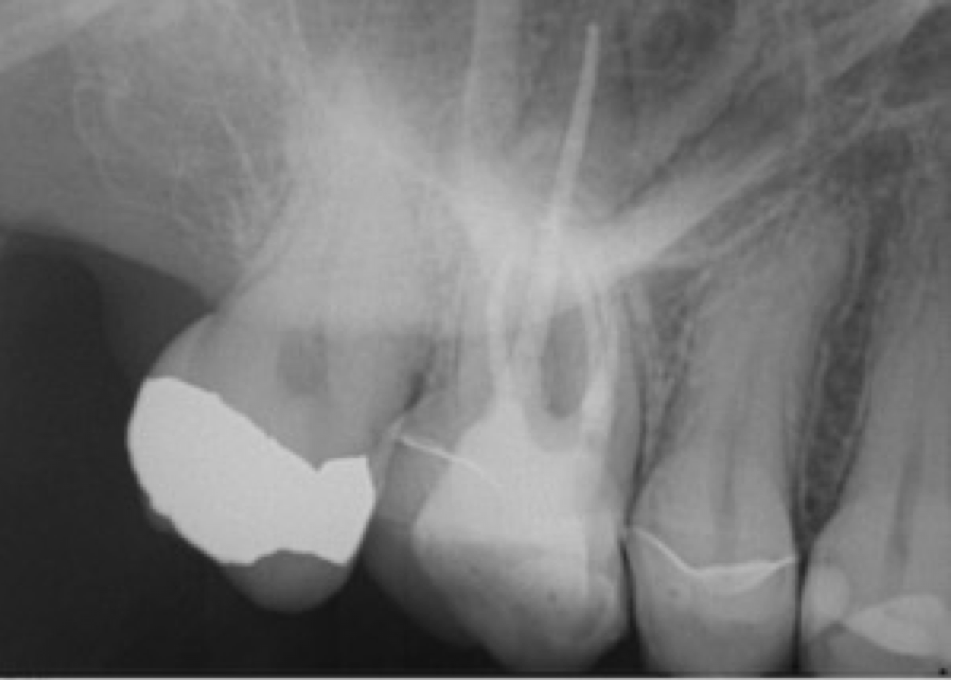

• Primärbehandlung Zahn 12

Parodontitis apicalis am Zahn 12 mit großer periapikaler Osteolyse als Nebenbefund eines Rö-Status vor PA-Therapie.

Echte Zysten sind eher selten. Meist handelt es sich auch bei so großen und relativ scharfbegrenzten Aufhellungen um Granulome. Granulome heilen im Gegensatz zu Zysten nach erfolgreicher endodontischer Behandlung meist knöchern aus.

Somit ist die Ersttherapie und in der Regel auch alleinige Therapie die orthograde Wurzelbehandlung.

Nur bei Fällen in denen die Osteolyse nicht rückläufig ist oder sich vergrößert, schließt sich eine Zystektomie mit apikaler Kürettage an.

Im vorliegenden Fall wurde der Zahn lege artis aufbereitet, desinfiziert und verfüllt. Die Röntgenkontrolle nach 6 Monaten lässt eine nahezu vollständige Ausheilung vermuten.

Die Brückenkonstruktion konnte somit auch erhalten werden.